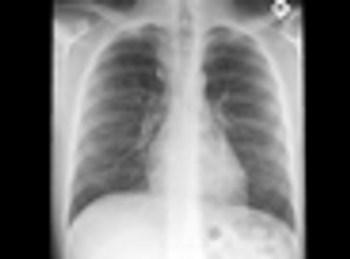

Hemoptysis in a Previously Healthy Young ManPublished: July 26th 2011 | Updated: